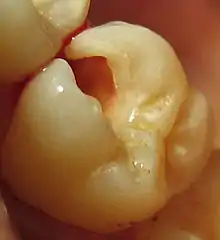

Tooth #3, the upper right first molar, with the beginning of a preparation. Looking into the preparation, the white, outer enamel appears intact, while the yellow, underlying dentin appears recessed. This is because the dentin was decayed and was thus removed. This portion of the enamel is now unsupported, and should be removed to prevent future fracture.